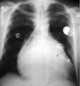

Median sternotomy

Median sternotomy is a type of surgical procedure in which a vertical inline incision is made along the sternum, after which the sternum itself is divided, or "cracked". This procedure provides access to the heart and lungs for surgical procedures such as heart transplant, corrective surgery for congenital heart defects, or coronary artery bypass surgery. [Source: Wikipedia ]